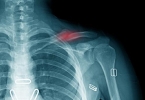

• 胸廓畸形能活多久

胸廓畸形能活多久

胸廓畸形的生存期与畸形类型及并发症相关,轻度畸形不影响寿命,严重畸形需手术矫正。1、遗传因素:部分胸廓畸形与基因突变相关,如马凡综合征、成骨不全症等遗传疾病可能导致胸骨凹陷或突出。基因检测可明确病因, ...